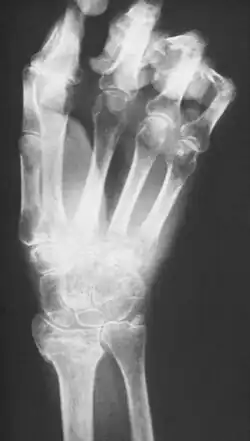

- faza III – pojawia się po kolejnych 3–6 miesiącach, przejawia się dalszymi zmianami zanikowymi skóry, która się staje sucha i towarzyszą jej przykurcze w obrębie stawów, co powoduje szponowanty wygląd kończyny, w badaniu RTG kości stwierdza się obecność plamistego zaniku.